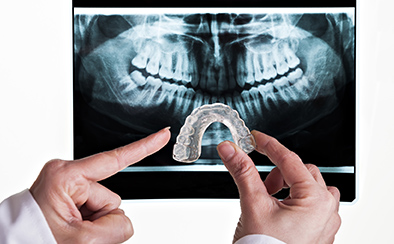

マウスピース矯正では治療前には各種設備を用いた検査、および治療のシミュレーションを行います。当院では歯科用CT、セファロ、口腔内スキャナー(iTero)などの各種先端機器を取り揃えており、精度高く検査した後、シミュレーションや治療計画の作成などに役立てております。

歯科用CT

口腔内スキャナー

セファロ